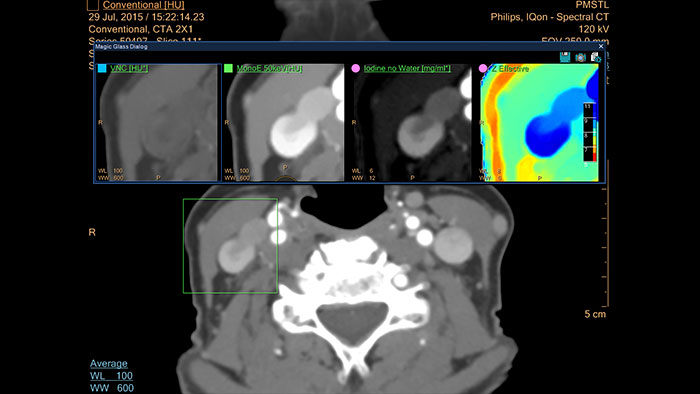

CT Spectral Viewer

IQon Spectral CT* Functionality

The spectral viewer is optimized for analysis of spectral data sets from the IQon Spectral CT Scanner. Obtain a comprehensive overview of each patient quickly and easily, quantify quickly, and assist in diagnosis. It is designed to accommodate general spectral viewing needs with additional tools to assist in CT images analysis.

Benefits

- Enhances the conventional image by overlaying an iodine map.

- Visualization of virtual non-contrast images.

- Images at different energy levels (40-200 keV).

- Switching to various spectral results can be done through a viewport control.

- Manage presets to create user/site-specific presets.

- Lesion characterization using scatter plots.

- Tissue characterization using attenuation curves.

* IQon CT reconstruction provides a single DICOM entity containing sufficient information for retrospective analysis - Spectral Base Image (SBI). SBI contains all the spectrum of spectral results with no need for additional reconstruction or post-processing. Spectral applications are creating different spectral results from SBI.